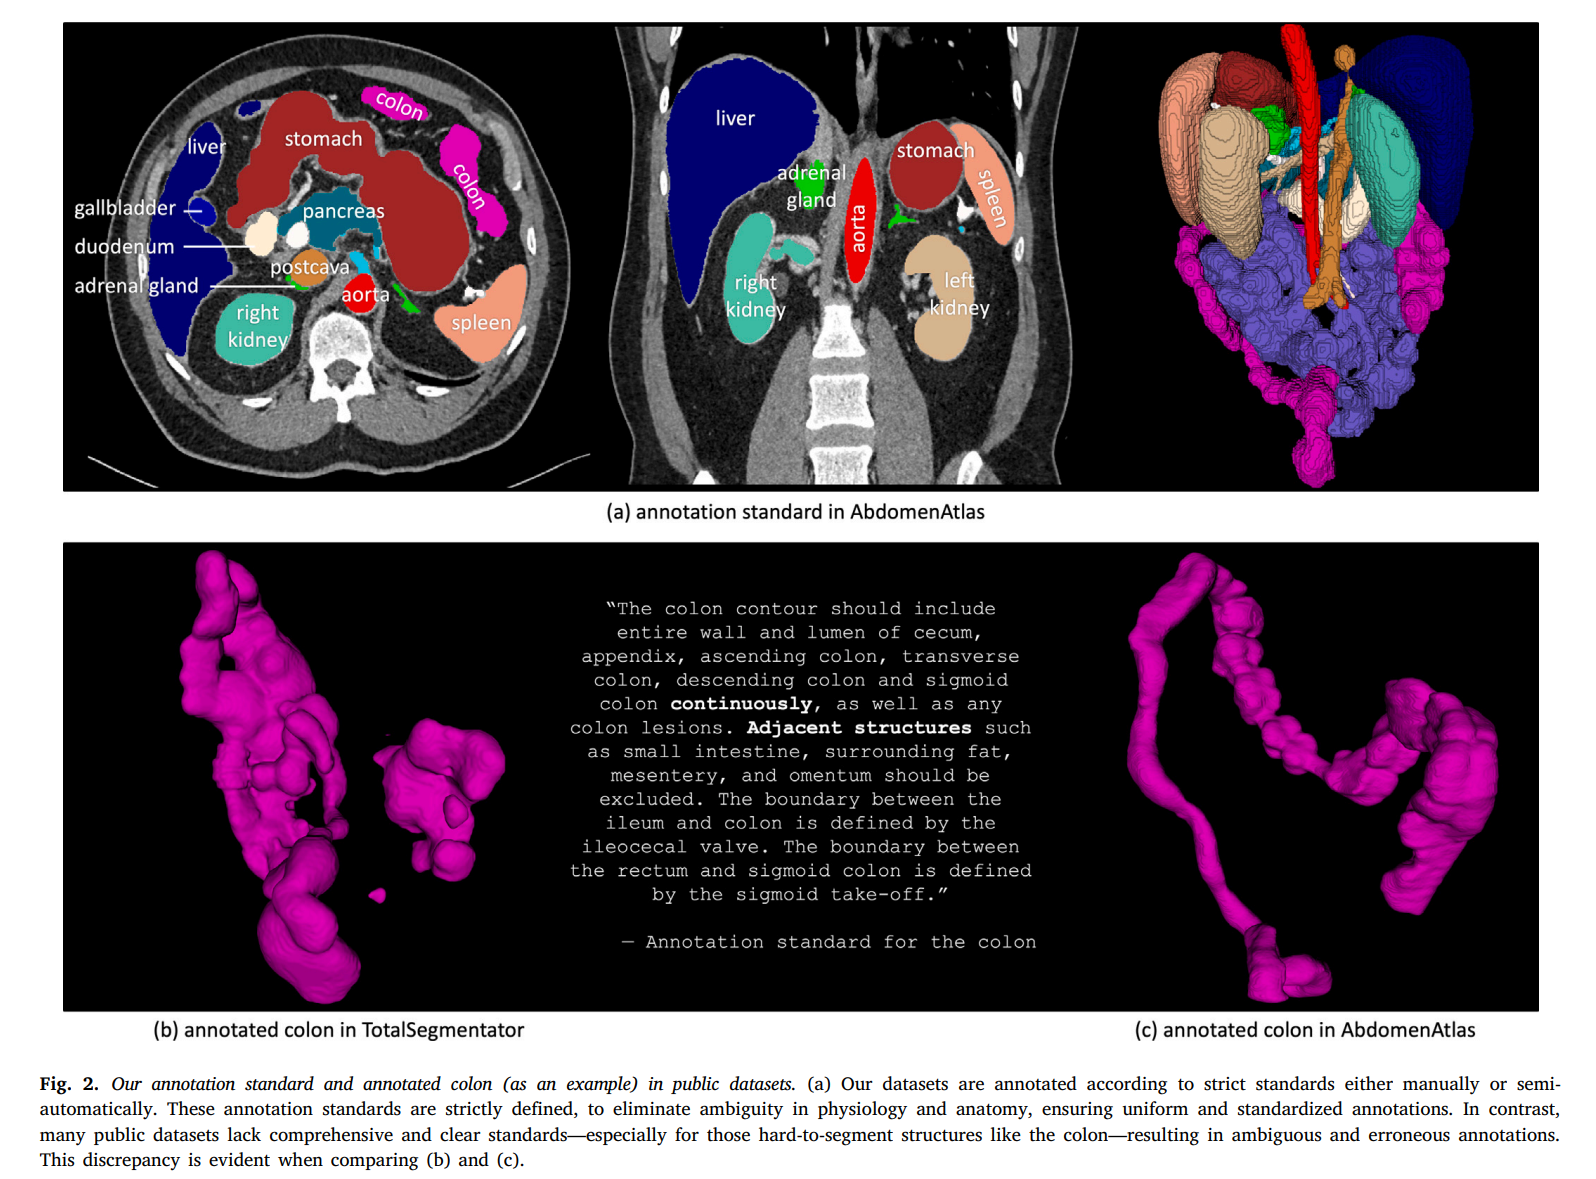

我们的研究招募了十名放射科医生,包括四名具有8至15年经验的资深放射科医生和六名具有3至5年经验的初级放射科医生。详细信息如表2所示。为了确保注释的准确性和一致性,所有放射科医生都熟悉了以下描述的注释标准。我们使用的工具包括Pair的许可版本和开源的3DSlicer进行注释和修订。我们为AbdomenAtlas中的25个结构提供了注释标准,包括16个腹部器官(食管、胃、十二指肠、肠道、结肠、直肠、肝脏、胆囊、脾脏、胰腺、左肾、右肾、左肾上腺、右肾上腺、膀胱、前列腺)、2个胸部器官(左肺、右肺)、5个血管结构(主动脉、腹腔干、下腔静脉、门静脉和脾静脉、肝血管)以及2个骨骼结构(左股骨和右股骨)。图2展示了一个详细注释的CT体积示例。

胃的轮廓应包括整个胃壁和胃腔,包括胃底、胃体、胃窦和幽门,以及任何胃部病变,同时排除相邻结构、器官和周围脂肪。十二指肠的轮廓应包括从十二指肠球部到Treitz韧带的整个十二指肠壁和腔,以及任何十二指肠病变,同时排除周围结构,如胰头、胆总管和周围血管。肠道的轮廓应包括从Treitz韧带到回盲瓣的空肠和回肠壁和腔,以及任何肠道病变,同时排除周围脂肪、肠系膜和肠系膜血管。结肠的轮廓应包括盲肠、阑尾、升结肠、横结肠、降结肠和乙状结肠的整个壁和腔,以及任何结肠病变,同时排除相邻结构、周围脂肪、肠系膜和网膜。直肠的轮廓应包括整个直肠壁、腔和任何病变,同时排除相邻结构、周围脂肪和肌肉。

AbdomenAtlas中手动注释的精度确保每个解剖结构都被明确定义,准确捕捉身体的难以分割的细节。如图2所示,AbdomenAtlas在难以分割的结构(如结肠)的精确手动注释方面表现出色,展示了与TotalSegmentator等数据集的明显优势,后者可能在注释中错误地包含相邻结构或注释不连续。尽管存在这些问题,TotalSegmentator仍然是一个有价值的数据集,因为在公共数据集中为难以分割的结构提供精确注释是罕见的。这主要是因为手动注释这些结构是一项细致且耗时的任务。没有一个公共数据集在5,246个CT体积中为这些结构提供手动注释,这使得AbdomenAtlas在规模和注释方面都脱颖而出。